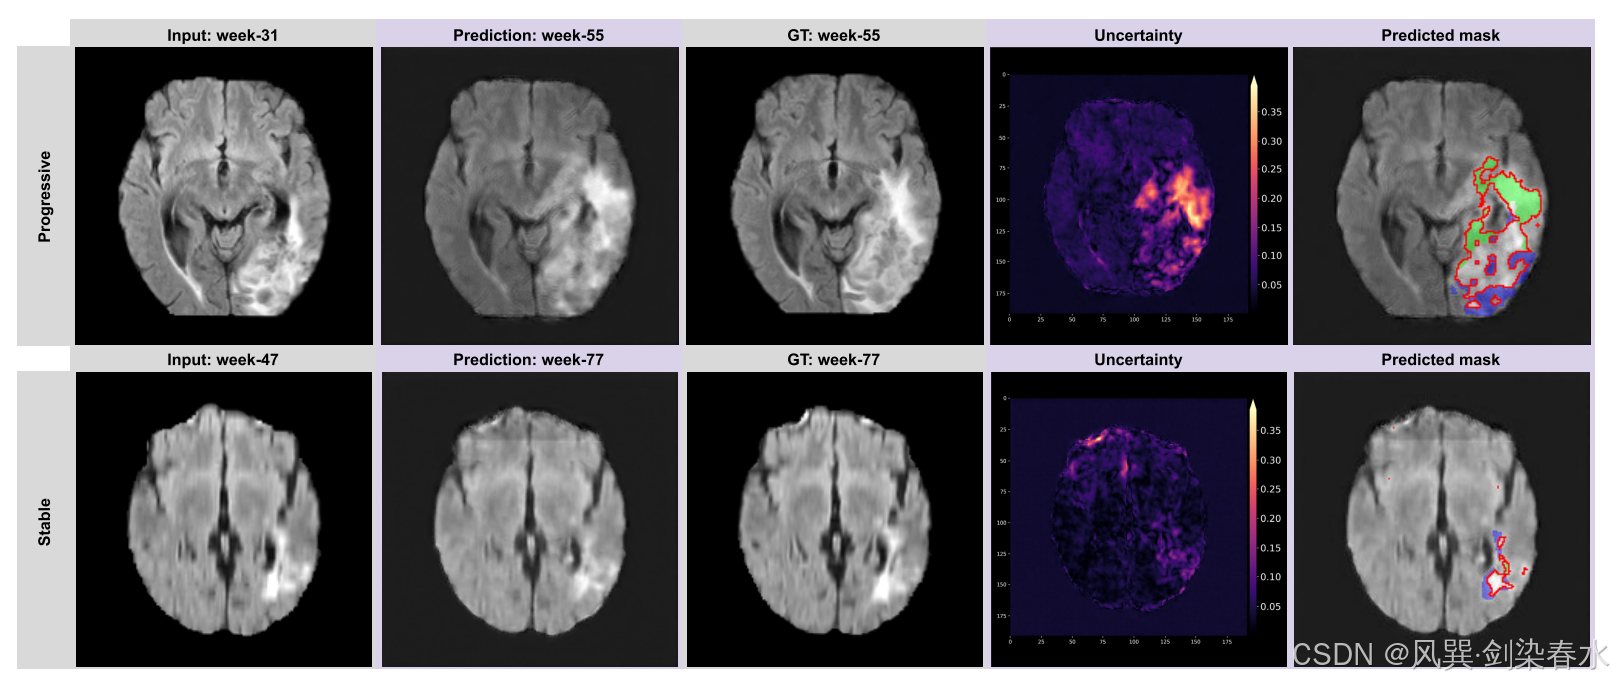

Figure 10 | 模型对外部测试数据集的预测示例:两个具有代表性的患者案例:一个(顶部)肿瘤呈进行性增长,另一个(底部)肿瘤保持稳定;在预测的肿瘤掩模中,绿色区域表示肿瘤的增长方向,蓝色区域则表示肿瘤的缩小方向;‘不确定性’图通过热图形式,在 MR 图像上突出显示预测中的不确定区域;

实验图还是太炫目了些~